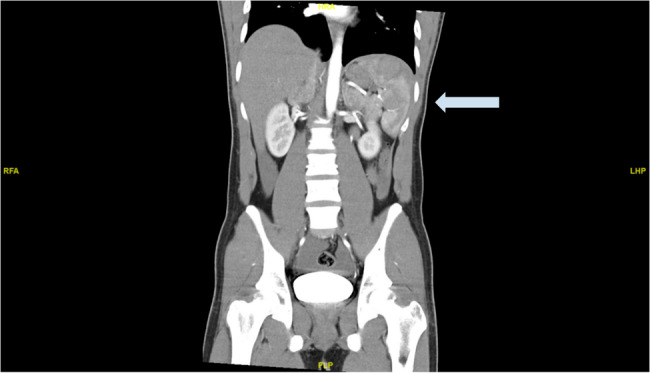

Case presentation: The patient is a 21-year-old male, with no known chronic disease. He is a smoker and complained of a persistent cough for the past three months. He presented the day after a gym session, with sudden left hypochondrium tenderness with no history of trauma, vomiting or diarrhoea. Physical exam revealed normal vital signs and generalized involuntary guarding over the entire abdomen. Initial point-of-care ultrasound was negative for free fluid in the abdomen, but a repeat ultrasound three hours later turned positive. Computed tomography scans of the abdomen, pelvis and mesenteric angiogram were then performed. They revealed intraperitoneal blood, a Grade III splenic haematoma involving the superior pole of the spleen towards the inferior pole, but no active bleeding. The patient was admitted for close monitoring. Initial laboratory evaluation did not show any coagulopathy or infection. The patient remained hemodynamically stable throughout his inpatient stay, and was managed conservatively with rest, analgesia, and empirical antibiotics. Serial haemoglobin levels remained stable, and his symptoms resolved with analgesia. As he remained hemodynamically stable, no repeat imaging was performed inpatient. He was subsequently discharged with instructions to avoid strenuous activities for 4 to 6 weeks. An outpatient follow-up was arranged for him, to review symptoms and monitor haemoglobin level.